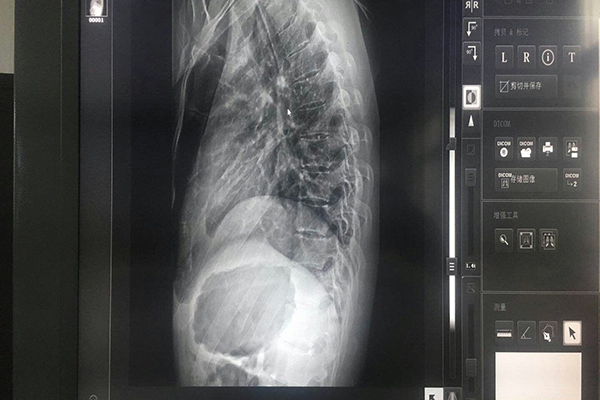

醫(yī)學(xué)灰階顯示器的亮度很高,這樣就可以拉開每一個灰階的差別,其亮度都在2百CD/M2以上;而彩色顯示器的亮度一般在100以下。彩色顯示器的原理是R、G、B三槍打出的三個電子束要通過一個蔭罩板(shadow?。恚幔螅耄┑?,在通過的時候,吸收或擋住了電子束的大部分能量,所以器亮度就大大降低;而灰階顯示器是電子束直接打到熒光粉上,能量的損耗就小,所以亮度比較高。

顯示器的亮度是會隨著時間而衰減的,普通顯示器由于沒有穩(wěn)定的亮度控制和校準(zhǔn),不但衰減較快,平時使用時,也由于受環(huán)境的影響,其亮度不能長時間的維持在一個對人體肉眼合適的水平上,而醫(yī)學(xué)灰階顯示器考慮到這一個問題,采取了穩(wěn)定的亮度控制技術(shù),對顯示亮度所反饋的信息隨時進(jìn)行校準(zhǔn),使其始終保持在標(biāo)準(zhǔn)亮度之上,符合臨床的閱片標(biāo)準(zhǔn)。